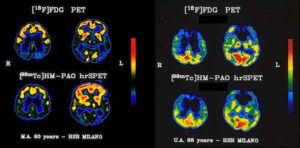

Una diagnosi più precoce del morbo di Alzheimer è un passo più vicina grazie a un team di ricercatori finanziati...